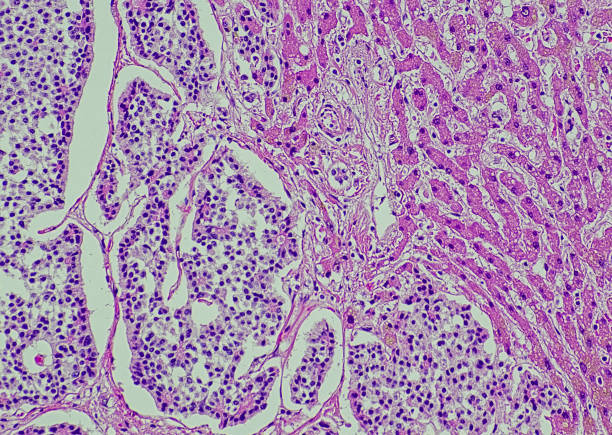

간경화 초기증상은 증상이 나타나지 않거나, 미미한 증상만 나타나기 때문에, 무시하고 지나치기 쉬운 경우가 많습니다. 하지만, 이러한 초기 증상을 간과하면 질병이 진행되어 치료가 어려워질 수 있습니다. 따라서, 간경화 초기증상을 발견하면 적절한 검사와 치료를 받아 조기에 질병을 예방하고 치료할 수 있습니다. 따라서 이번 시간에는 간경화 초기증상에 대해 자세히 알아보도록 하겠습니다.